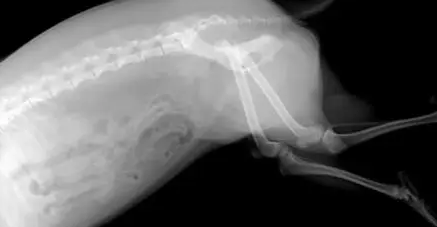

如果狗狗受伤比较严重,比如骨折、骨裂、撕伤、内脏损伤等,这种情况自愈的概率就不是很高,需要带到宠物医院治疗,并根据严重的程度看需不需要手术治疗。另外,如果狗狗的伤口比较大并且面积较深,这种情况也是不能自愈的,需要立即给狗狗进行进行创口周围和创面处理,不然很可能会继发严重的感染,甚至威胁狗狗的生命。